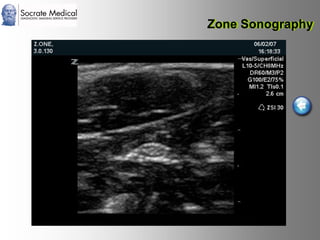

Il documento presenta la tecnologia della zone sonography, che promette una rivoluzione nel campo degli ultrasuoni, superando i limiti dei sistemi tradizionali grazie a metodi di acquisizione dati più veloci e una gestione delle informazioni migliorata. Questa tecnologia consente una maggiore definizione dell'immagine, una riduzione degli artefatti e un'ottimizzazione del processo diagnostico, con vantaggi in termini di tempo e costi. Inoltre, il channel domain processing e la zone speed technology offrono applicazioni avanzate e miglioramenti nella sicurezza diagnostica.